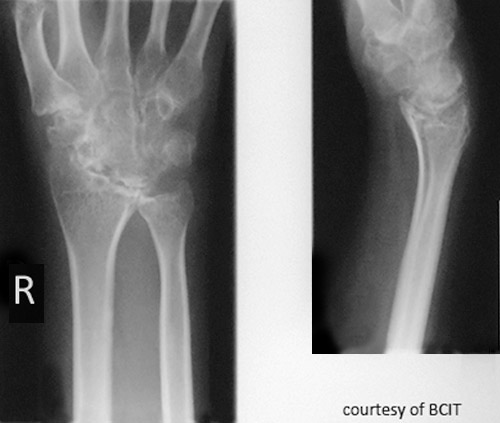

Radiographic signs of gout?

Late changes: “mouse-bitten” erosions, overhanging edges, possible calcified tophi; no osteopenia.

Radiographic signs of RA?

Early: minimal bony change; later: osteoporosis/rarefaction, deformities.